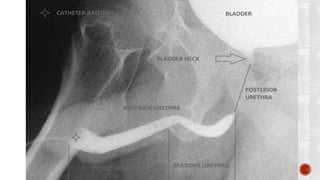

 Plain film :

 causes of stricture-

 pelvic trauma(pelvic bone fractrues)

 spinal cord injury(lumbar spine fracture)

 prostatic carcinoma mets to bones(stricture at prostatic level)

 Anterior :

 penile

 bulbar

 Posterior :

 membranous

 prostatic

 Verumontanem

 Bulbomembranous junction at the level of the inferior margin of the obturator

foramen